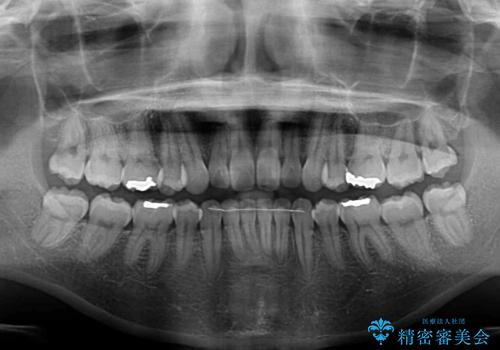

- 30代女性

- 1年8ヶ月

治療途中で出産をされたため、通院が困難となりましたが、インビザライン・ライトでの治療可能期限である2年以内に無事に治療を終えることができました。